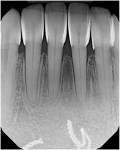

Approximately 3 years after maxillary black triangle closure, the patient returned to discuss closing her persistent mandibular black triangles. At this time, the measurement from the interproximal contact to the crest of bone ranged from 7.5 to 8 mm. This measurement, paired with the length of time that she had been out of orthodontics, suggested the papilla was never going to fill in on its own. Having already experienced the predictability of this procedure, the patient was excited to proceed with treatment to close her lower black triangles (ie, teeth Nos. 22 to 27) (Figure 3 through Figure 5).

The finishing process is started with the use of discs. Using the existing tooth structure as a guide, both large and small contouring and polishing discs (Sof-Lex™, 3M) are used to finish the composite to the tooth (Figure 17). Next, a fine, long flame-shaped diamond bur is used dry to aid this process on the buccal aspect, keeping the bur in the long axis of the tooth (Figure 18). On the lingual aspect, a 7404 carbide bur is used to remove flash in the cingulum area and lingual concavity. Next, the gingival margins on both the buccal and lingual aspects are marginated using a #12 scalpel blade (Bard-Parker®, Aspen Surgical). When necessary, a mosquito-shaped fine finishing diamond bur is used wet with a light, deft touch, being careful not to gouge the root surface (Figure 19). This is done with extreme care. Following this, a sharp polishing point (Brownie®, Shofu Dental Corporation) is used wet with a gentle touch over all accessible composite margins (Figure 20). Final polishing is completed using polishing cups (Figure 21), and floss and an x-ray image are used to check for any gingival overhangs (Figure 22). Although the tissue will be slightly irritated from the finishing process, it will heal completely within a few weeks. The result is both seamless and beautiful. (Figure 23 through Figure 25).